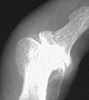

RA

- ++

Rheumatoid Arthritis

++

+++